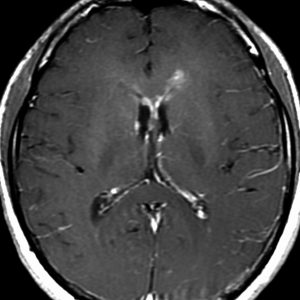

左はICE化学療法 (IFO/CDDP/VP-16)前,右は1コース終了後です。腫瘍は顕著に縮小してgerminomaとして普通の化学療法反応性を示します。また,松果体と下垂体には腫瘍はありません。

ICEを3コース行なって腫瘍は完全消失して,前頭葉浮腫も消えました。その後に,全脳照射 25.2Gy/14分割を加えました。無症状で復職することができました。